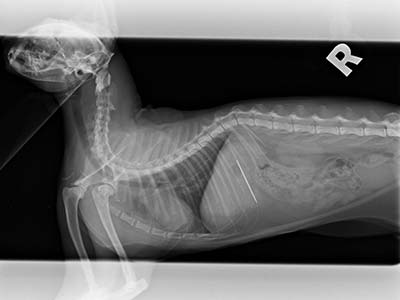

本病歷的小貓咪就是趁媽媽不在偷跑去玩線,媽媽回來後發現小貓一直乾嘔而帶來醫院就診,在X光下赫然發現胃裡有一根針!和醫師討論後手術利弊後,決定使用可以馬上回家且無創的內視鏡手術將異物取出。麻醉甦醒後,小貓很快恢復了精神活力,好像什麼都沒發生過,開開心心的回家了。

X光可以看到胃中有一根針

仰照也可以看到針的位置